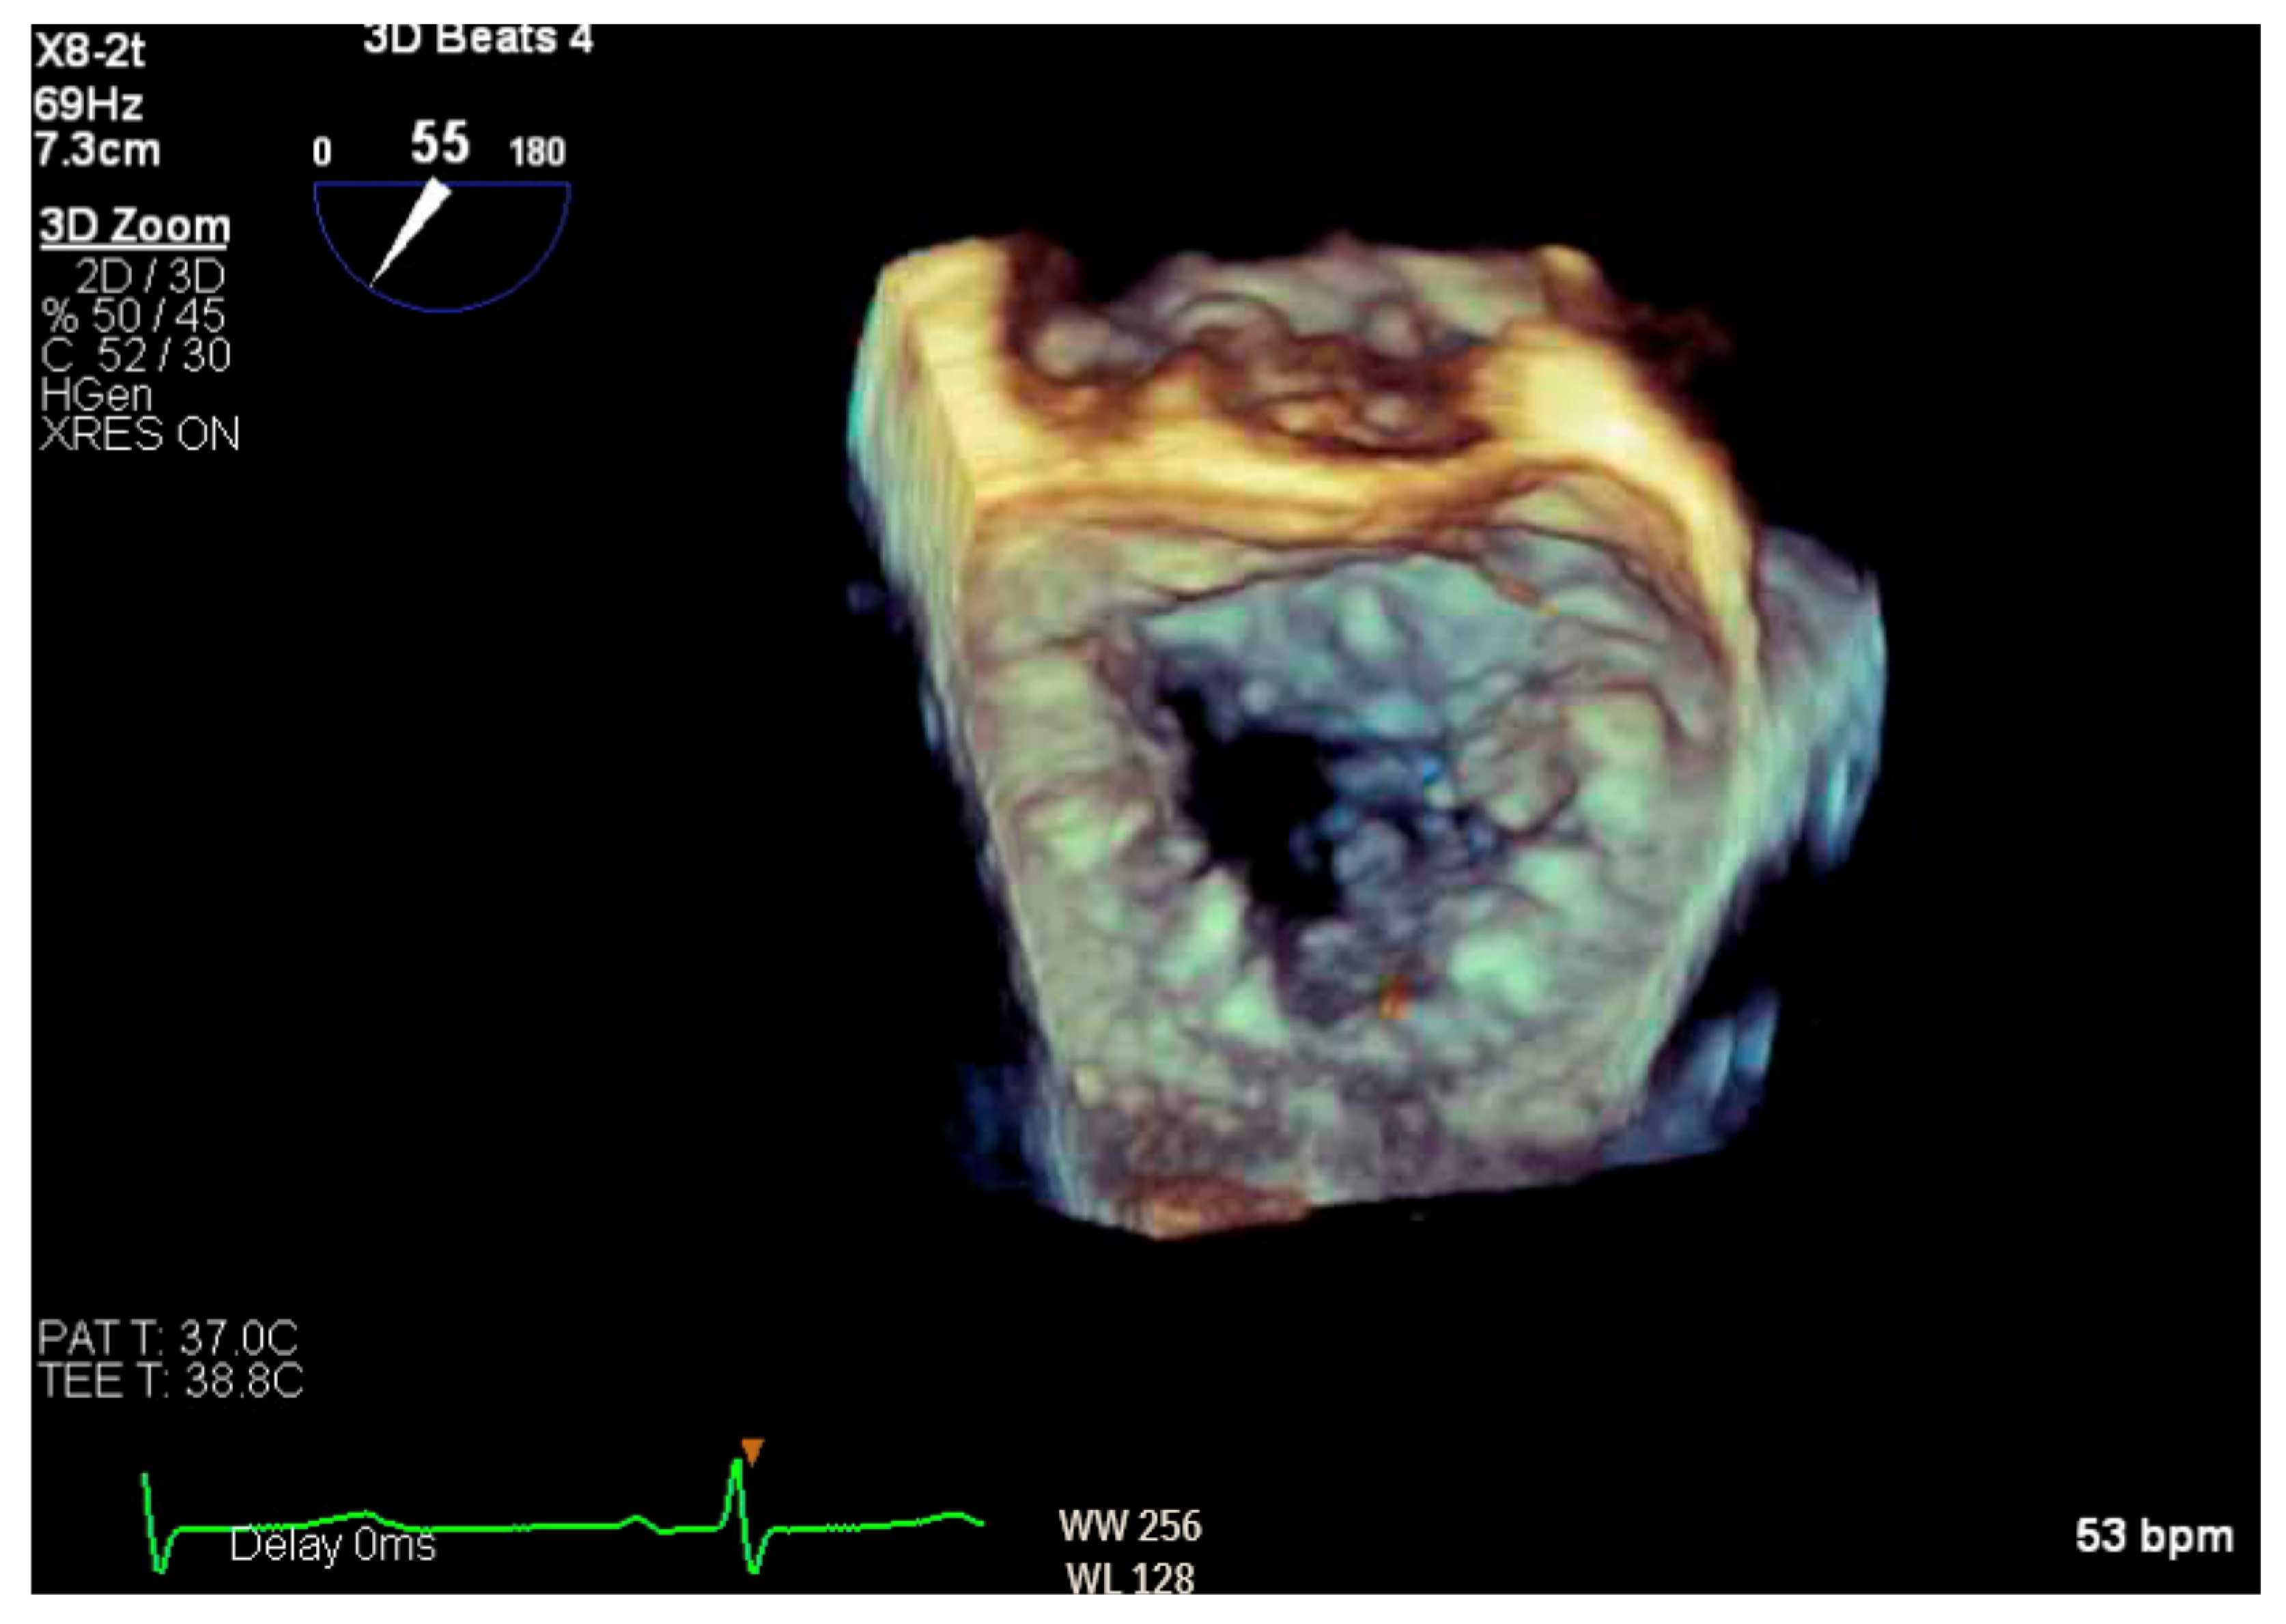

Figure 6.

Three-dimensional reconstruction of mitral valve showing anterior leaflet prolapse and flail.

Given the concern for primary MR, a transesophageal echocardiogram (TEE) was performed for further assessment. The study showed prolapse, chordal rupture and partial flail of the A3 leaflet with an area of non-coaptation and severe MR (Figure 6, Supplementary Video S4). Quantification using the proximal isovelocity surface area method revealed an effective orifice area of 0.46 cm2 and a regurgitant volume of 80 milliliters with notable systolic pulmonary vein flow reversal, consistent with severe Carpentier class II MR from prolapse and flail (Figure 7, Supplementary Video S5) [2]. This highlights the role of TEE and 3D imaging in assessing for SAM-independent causes of primary MR in patients with HCM. A TTE alone can miss these anatomical findings, especially in medial (A3 or P3) or lateral (A1 or P1) mitral scallops.